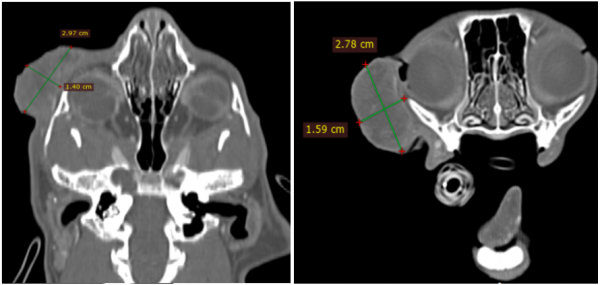

추가로 진행한 CT 검사상에서도

우측 안면부 종괴가 악성 고양이 비만세포종(high grade MCT)으로 의심되었으며,

비장 결절도 전이성 비만세포종 가능성을 배제할 수 없었습니다.